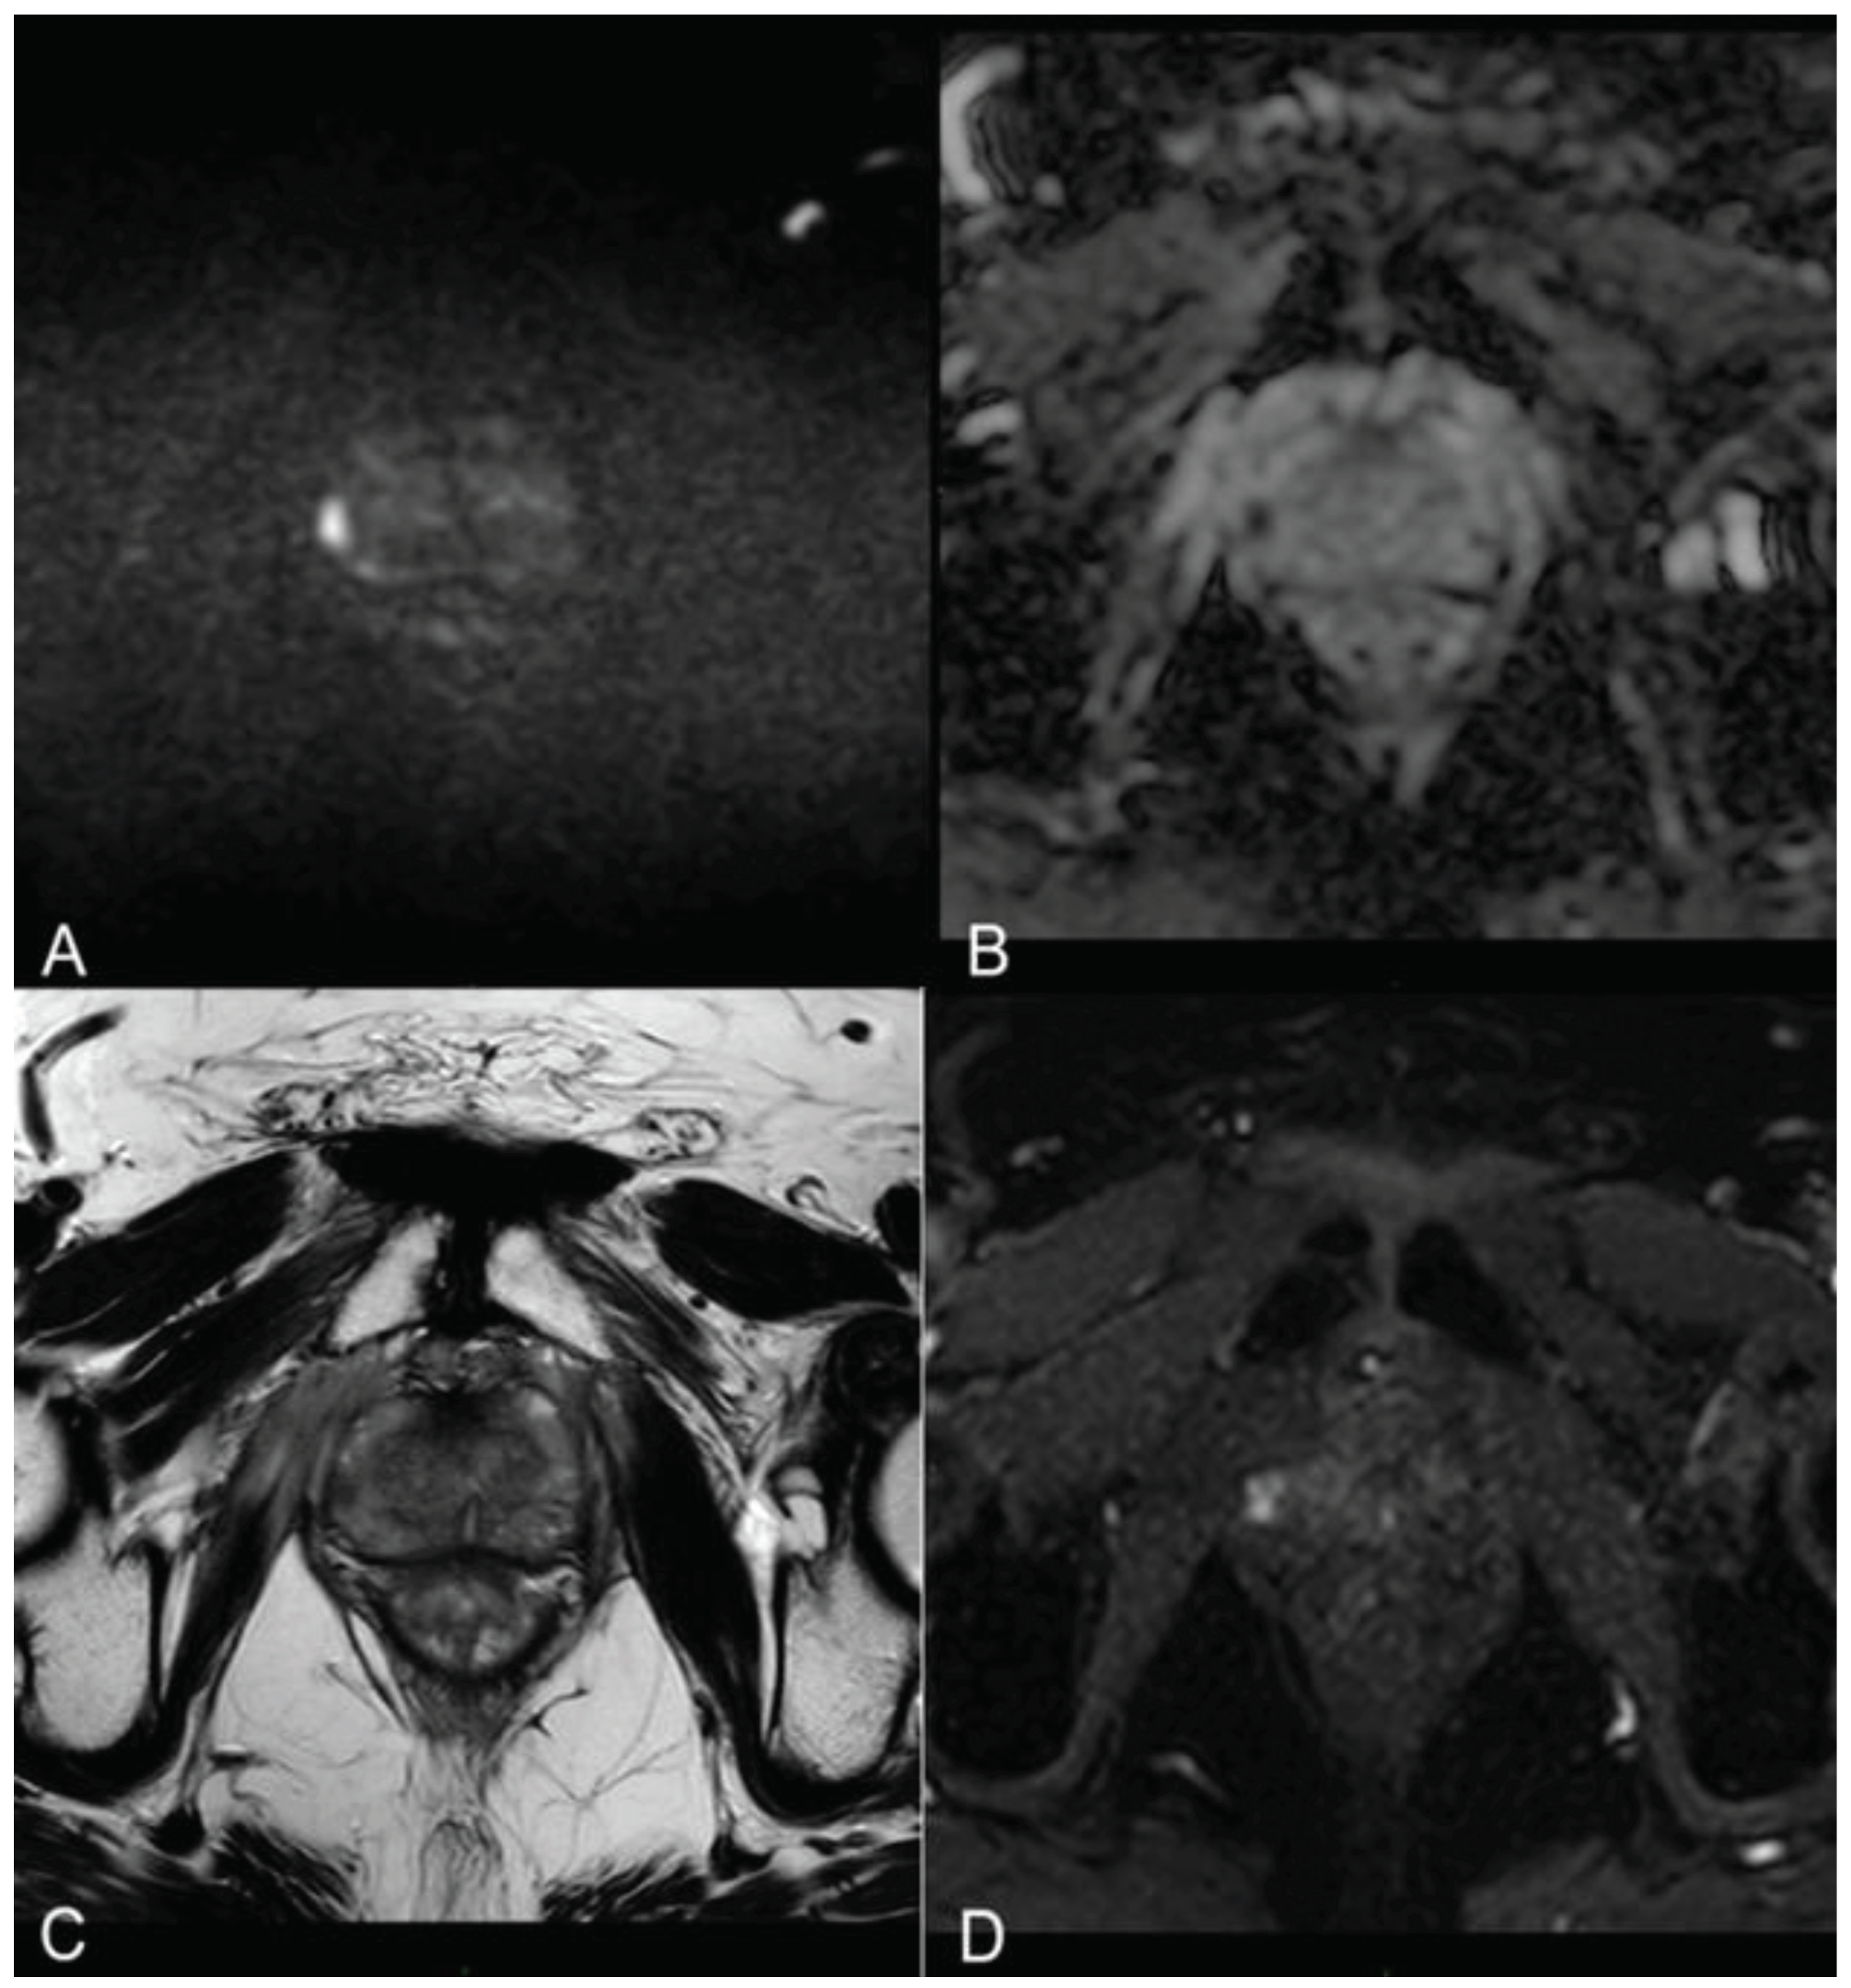

The pre-procedural evaluation consisted in electrocardiogram, complete blood count, urine examination and urine culture, evaluation of post-voiding residue and uroflowmetry. Patients were also submitted to IPSS-QoL and IIEF-5 questionnaires at baseline and during follow-up to investigate any procedure-related erectile dysfunction or urinary symptoms. Given that the procedure was guided by MRI/US fusion images, a 3T multiparametric prostate resonance (mpMRI) scan was performed for each patient at Time 0, adhering to the protocol delineated in Table 2 (refer also to Figure 1).

Figure 1. (a, b) Diffusion-weighted Imaging (DWI) b-value 2500 s/mm2 and ADC map on axial plane showing focal marked hyperintensity on high b-value DWI sequences corresponding to a hypointensity on the ADC map (PI-RADS 4). (c) T2-weighted TSE sequence on axial plane showing an hypointense lesion in the peripheral zone of the right middle portion of the gland. A curvilinear contact surface with the prostate capsule is demonstrated without any sign of capsule invasion. (d) Dynamic Contrast-Enhanced Imaging (DCE) with T1-weighted Dixon sequence with fat suppression on axial plane: early and significant focal enhancement in the peripheral zone of the right mid-portion of the gland.